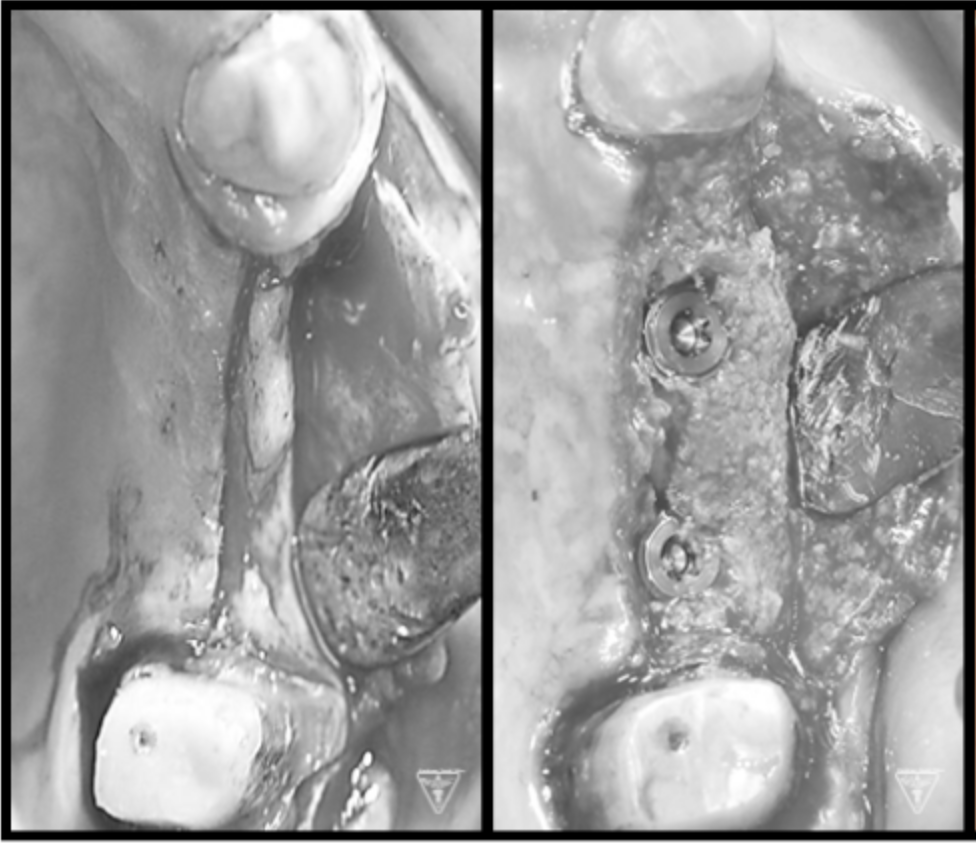

骨再生治療